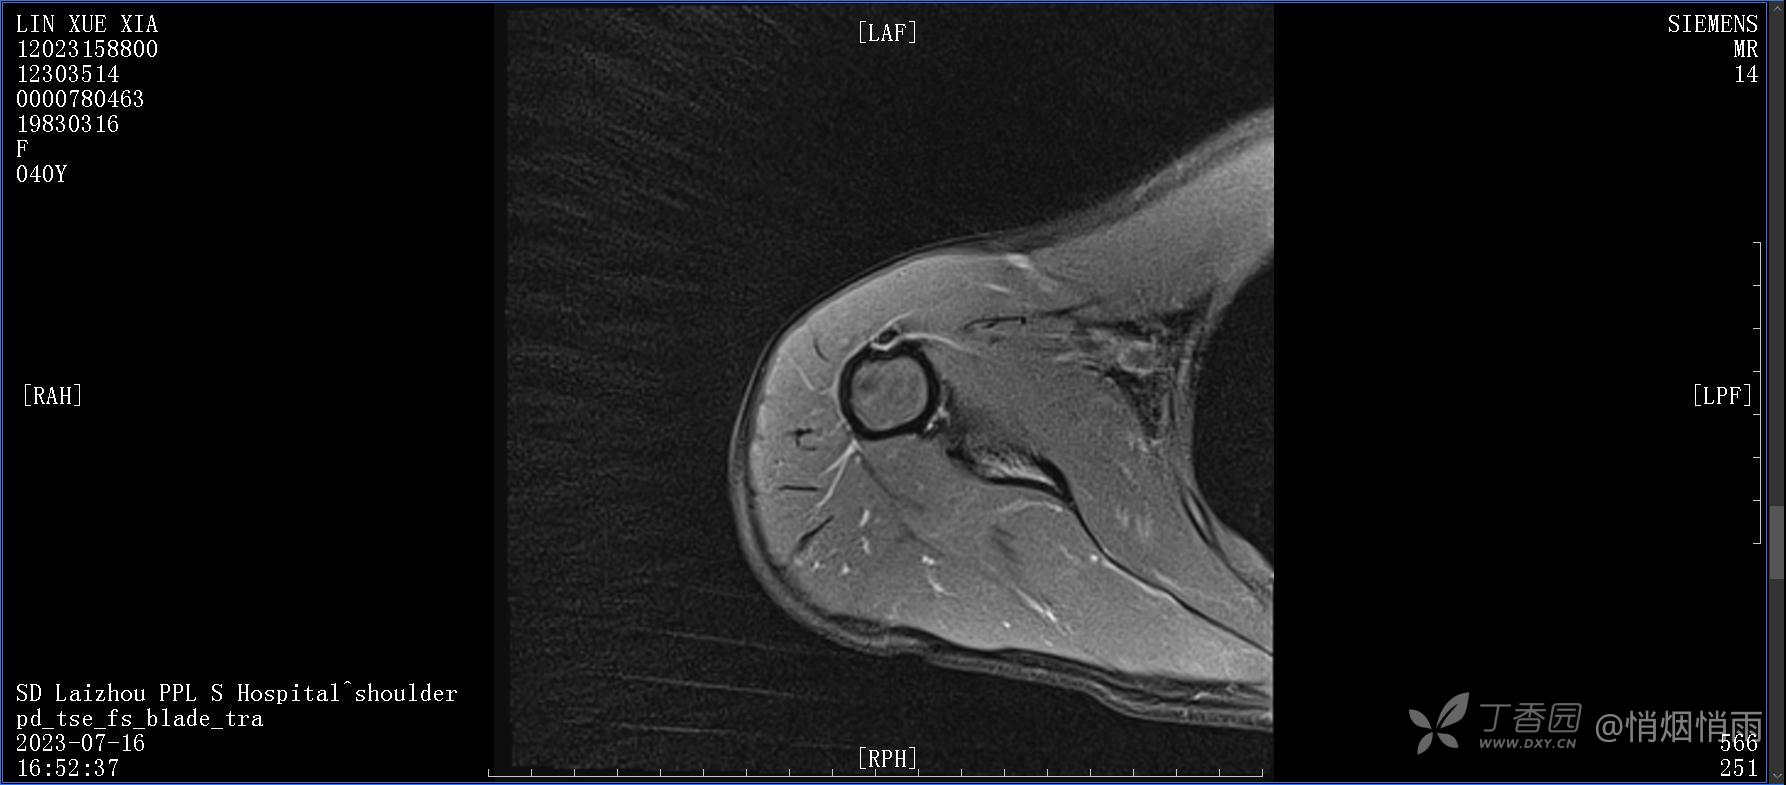

查体:右肩关节局部轻度肿胀,肩胛区压痛明显,痛处不固定,肩关节痛性活动受限,jobe test(+),lift -off test(+),中指、环指感觉较余指减退,余肢端感觉及血运情况可。

目前的诊断,暂时依据辅助检查诊为肩袖损伤,但是患者疼痛的性质和特点,却不是单纯的肩袖损伤所致。考虑过胸廓出口综合征,但是该疾病会出现肩胛区的疼痛吗?(由于考虑到费用的问题,没再进行下一步的检查)带状疱疹会有如此的症状吗?